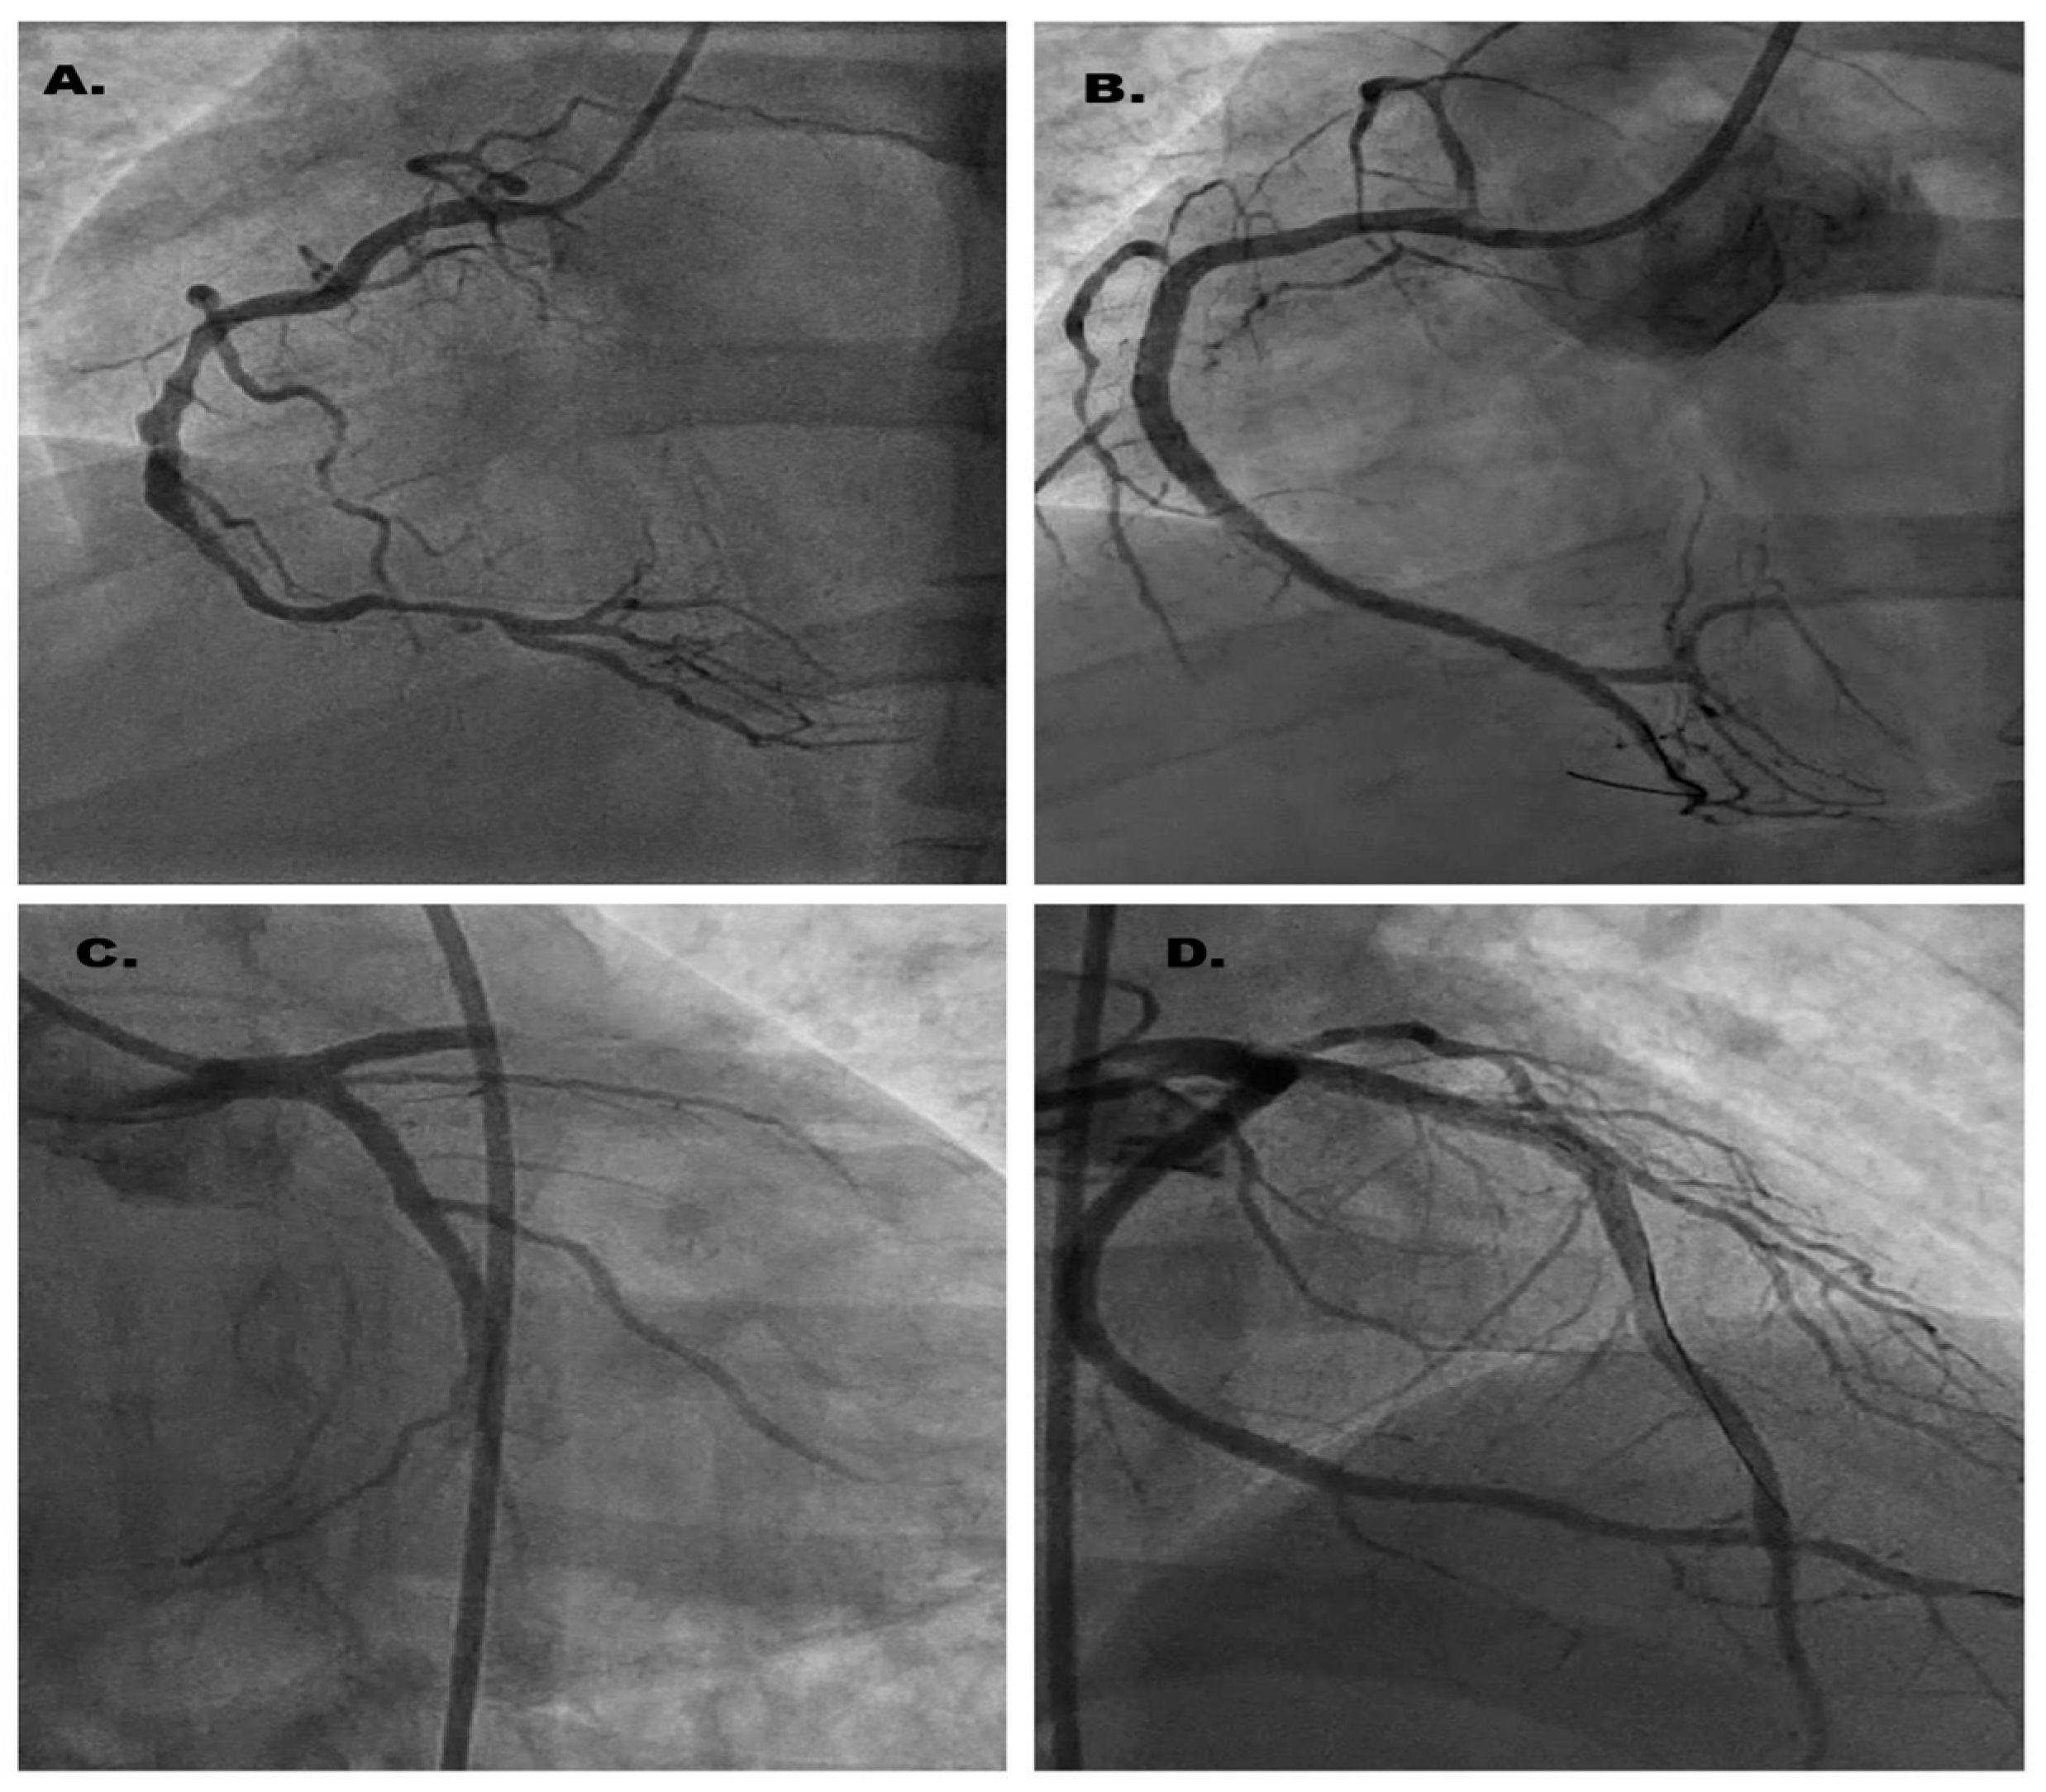

2. Case Report